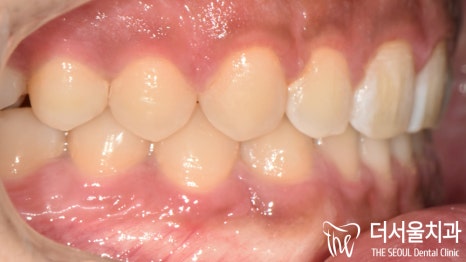

이제 아랫니가 많이 보입니다.

올바른 피개량을 갖게 되어

이전에 비해 훨씬 편안하고

안정적인 모습으로 바뀌었습니다.

절단연부터 느껴지는 비대칭도

상당 부분 나아진 것을 볼 수 있으며

정중선도 알맞게 일치하고 있네요.

구치부 교합도 훨씬 긴밀해졌으며

톱니바퀴와 같이 잘 물리고 있는 모습입니다.

전체적으로 정상 교합으로 바뀌었는데요.